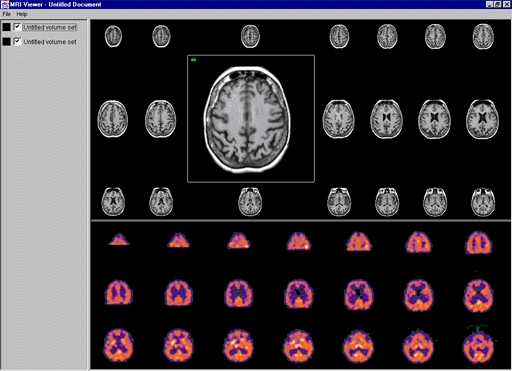

USAA ~ Safeway ~ Limited Brands ~ Macy's ~ Sears ~ Emporium ~ Nokia ~ Motorola ~ Samsung ~ LG ~ BlackBerry ~ HTC ~ Wal-Mart Stores ~ CVS ~ Best Buy ~ Rite Aid ~ Nike ~ GAP ~ J. C. Penney ~ Chevron ~ General Electric ~ AT&T ~ Hewlett-Packard ~ Bank of America Corp. ~ Citigroup ~ Berkshire Hathaway ~ International Business Machines ~ McKesson ~ Kaiser Permanente ~ Kaiser Hospitals ~ U.C.S.F ~ Stanford University School of Medicine/Medical Center ~ Sutter Healthcare ~ California Pacific Medical Center ~ San Francisco General Hospital And Medical Center ~ San Francisco VA Medical Center ~ U.S. Department of Transportation ~ U.S. Department of Homeland Security ~ Exar ~ Boeing ~ AIS ~ Siemens ~ Kaiser People Solutions ~ Cardinal Health ~ Procter & Gamble ~ UnitedHealth Group ~ Kroger ~ Marathon Oil ~ Costco Wholesale ~ Home Depot ~ Target ~ Johnson & Johnson ~ Morgan Stanley ~ State Farm Insurance ~ Dell ~ Boeing ~ Microsoft ~ Walgreen ~ United Technologies ~ Dow Chemical ~ MetLife ~ Wells Fargo ~ United Parcel Service ~ Caterpillar ~ Lowe's ~ Sears Holdings ~ Cisco Systems ~ Johnson Controls ~ FedEx ~ Intel ~ Sysco ~ Comcast ~ Coca-Cola ~ American Express ~ Aetna ~ Motorola ~ Allstate ~ Prudential Financial ~ Tyson Foods ~ Staples ~ Delta Air Lines ~ City and County of Sacramento ~ City and County of San Francisco ~ City and County Oakland ~ San Jose International Airport ~ JFK International Airport